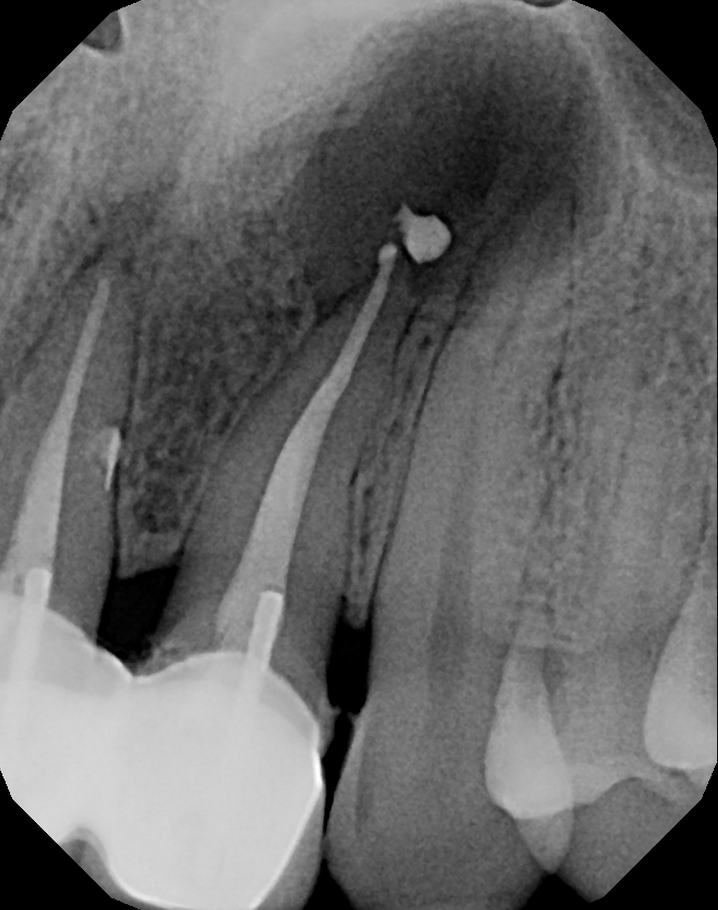

#7 NS-RCT (with SI retrieval)

Dx: Previously Initiated with CAA